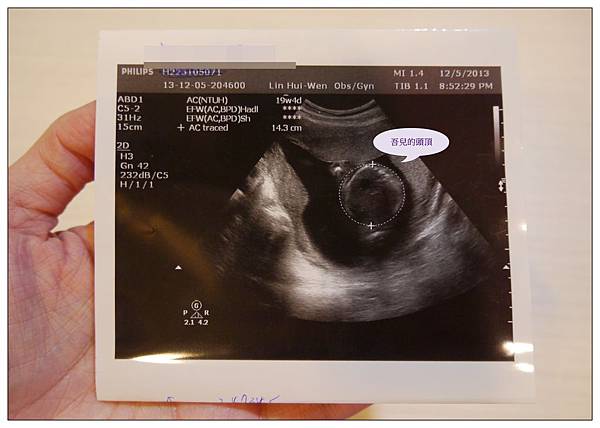

這次是第三次的正式產檢囉!!

原本之前都是一直在許世賓婦產科做產檢的~~

但喵娘和婆婆都覺得還是要去大醫院生小孩比較放心

所以小菲只好換到小菲妹之前產檢的林慧雯婦產科~~這樣生的時候就會是在台北的國泰醫院

林慧雯醫生也是很知名的婦產科女醫生~~~

20周的蔡小球因為身體器官都已經逐漸發展完成~~

所以醫生這次照超音波就照得很仔細~~除了胎心音之外

從頭檢查到眼睛、鼻子、手指頭、腳趾頭、脊椎、胃全部一一指出來給我們看

換到林慧雯這裡產檢的好處就是每次都可以拿到三張的超音波照片~~~

許世賓都只有一張而已~好小氣喔XDDD

這張是蔡小球的頭頂~~周數大約是20W5D(頭比較大的意思??XD)